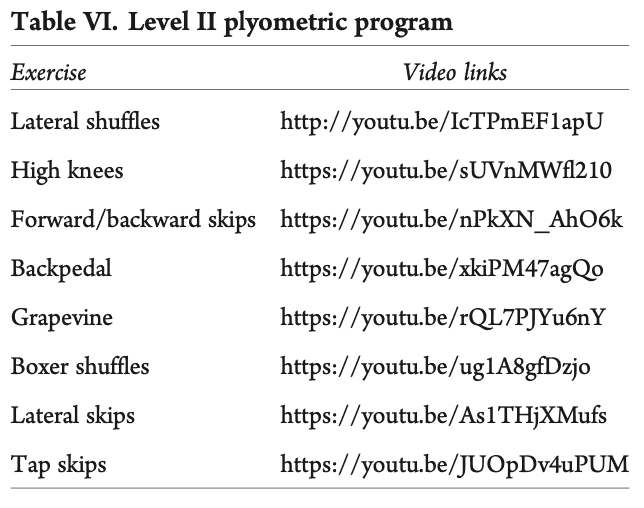

如果参与者成功完成了第一阶段和第二阶段的 I 级负重训练,行走时不会一瘸一拐,并且在日常活动中没有疼痛感,就可以进入步行/跑步计划。 这里的建议也是在跑步机上启动该计划。 必须遵守以下规则(i)不爬山或上坡,(ii)不做速度练习,(iii)练习姿势,(iv)每隔一天跑一次。 理想情况下,他们应继续进行二级和三级负重训练。